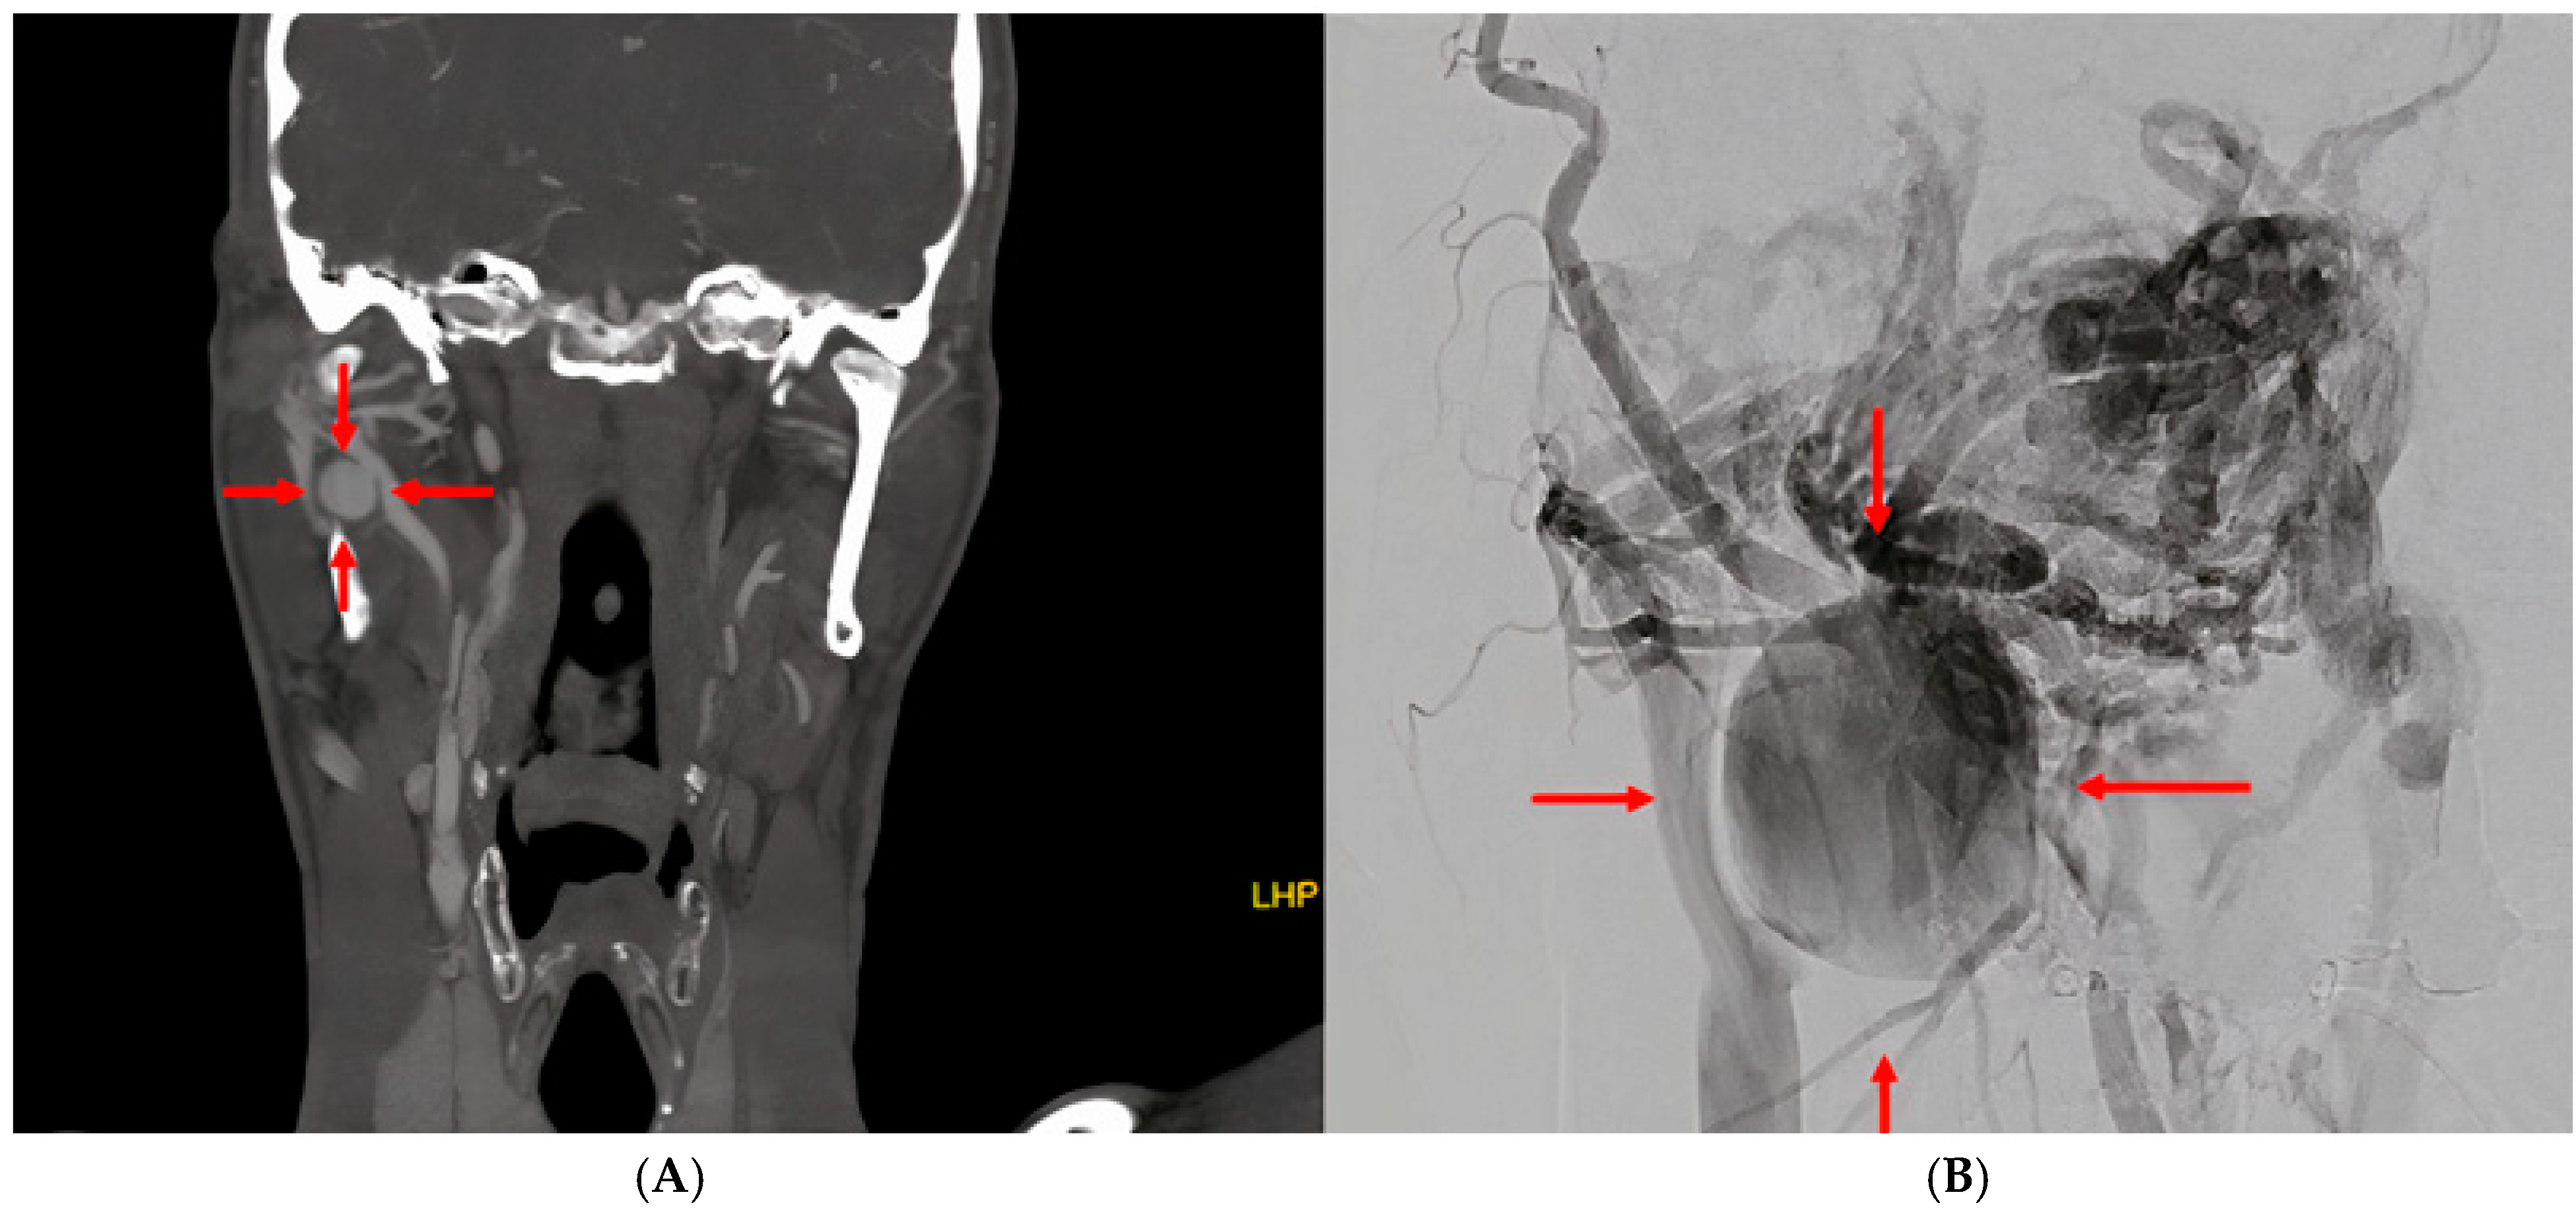

2. Case Report